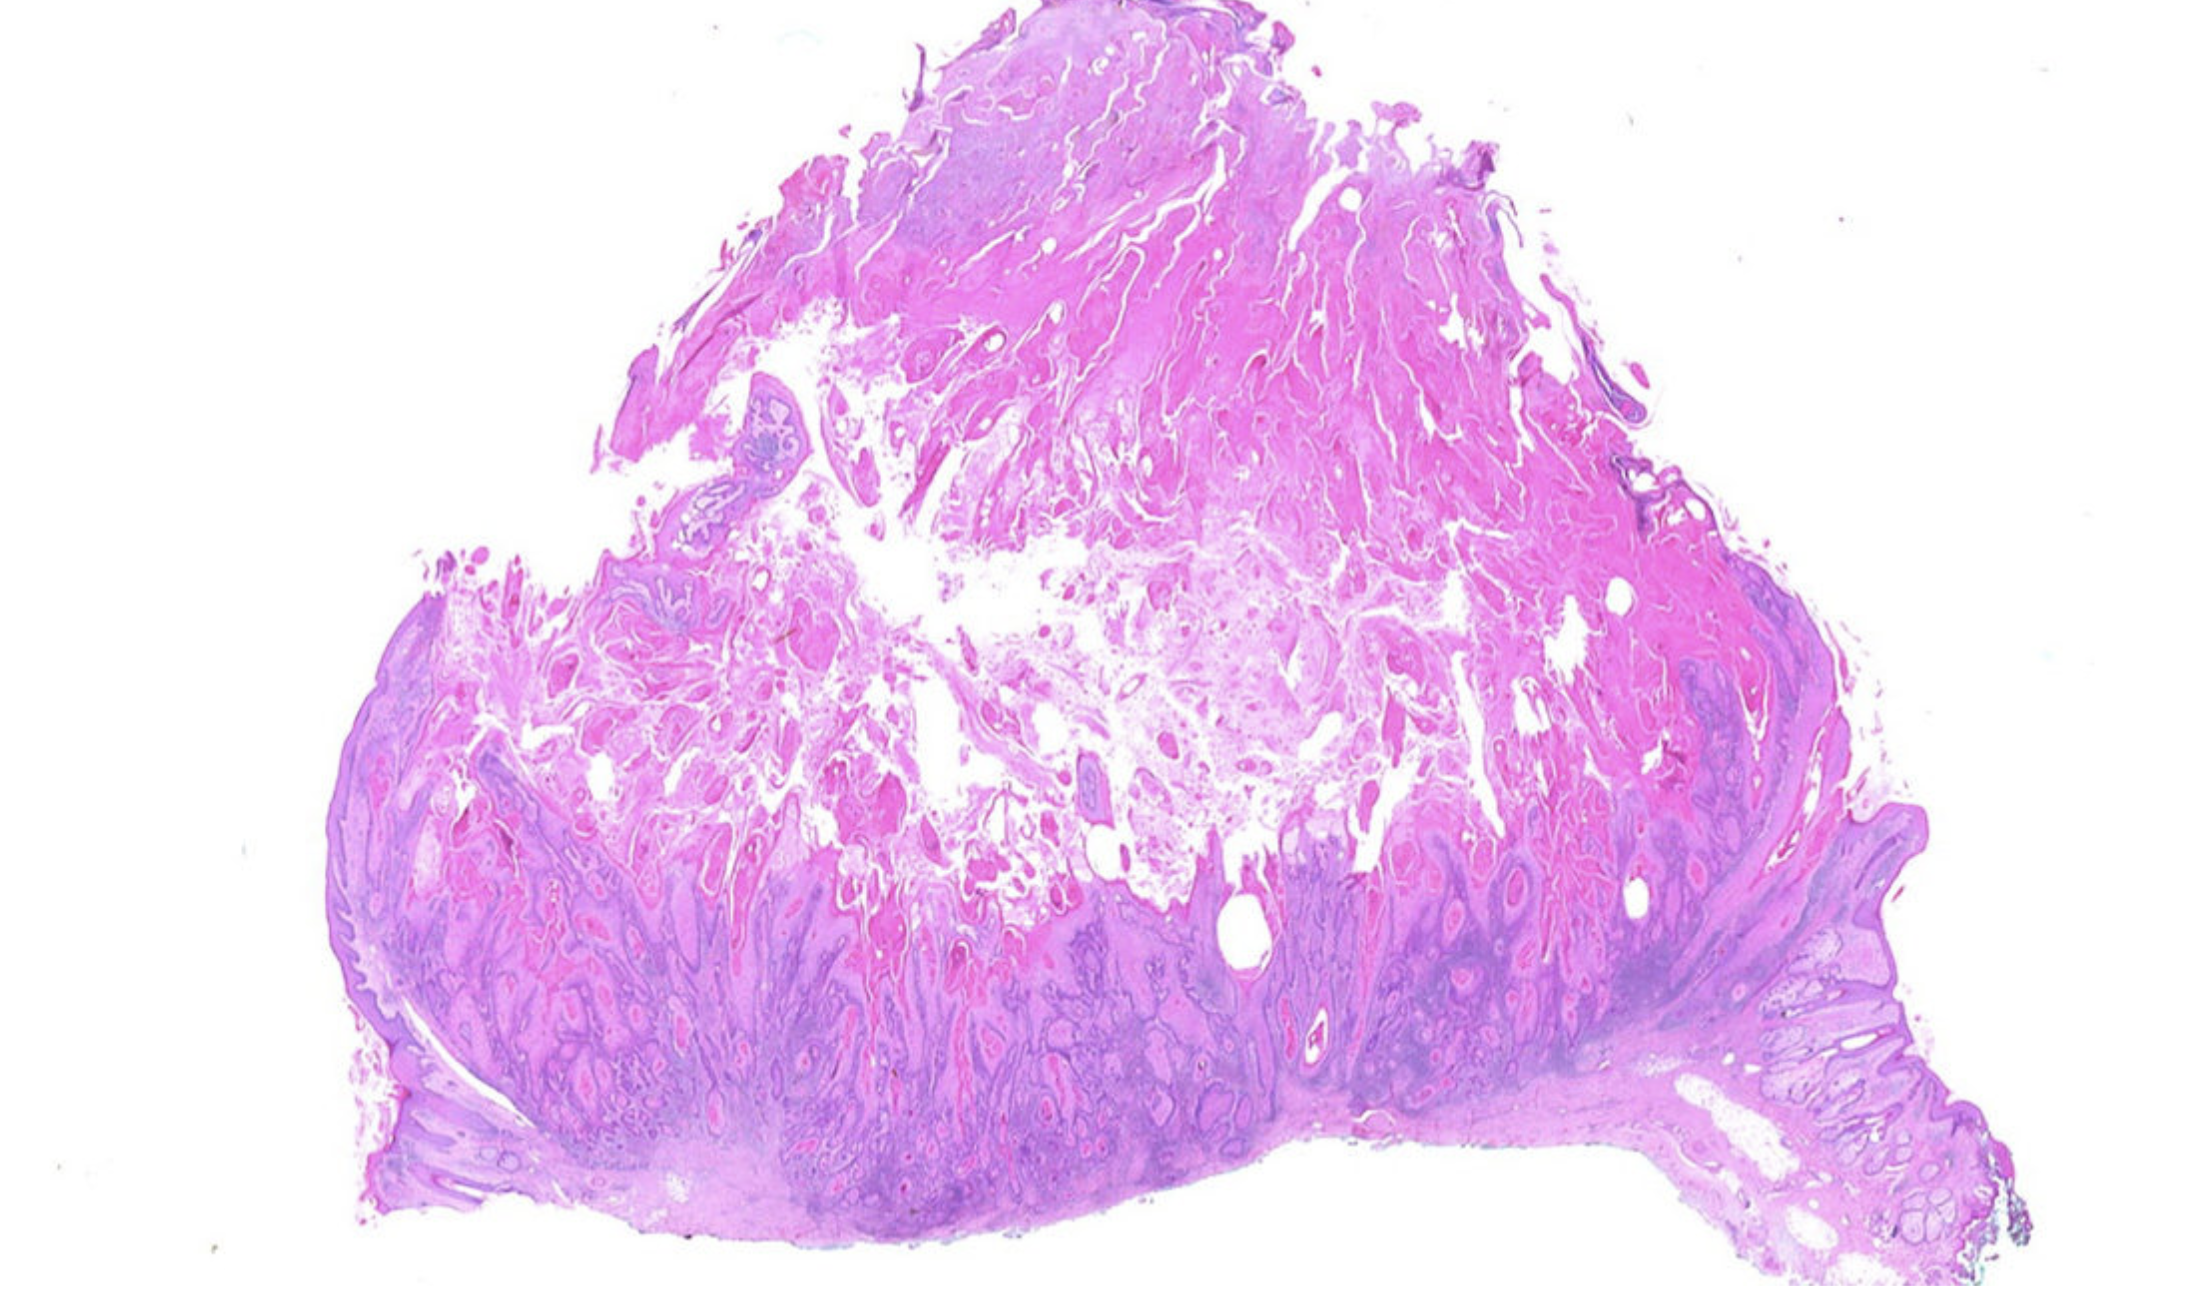

3. Под микроскопом: лаборатория Top Pathology Lab объединяет источники данных для разработки ИИ, обнаруживающего рак.